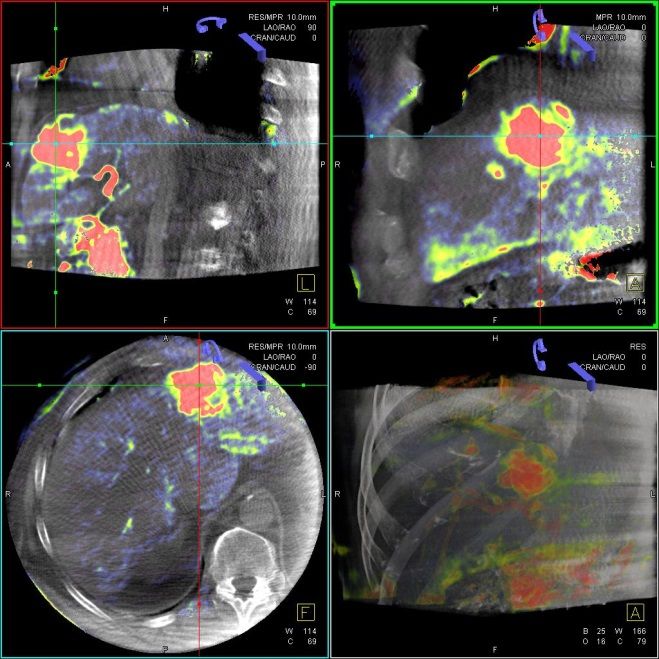

Selektive Interne Radio-Therapie (SIRT)

Die Selektive Interne Radiotherapie (SIRT) wird in der Fachliteratur auch Radioembolisation (RE) genannt. Hierbei werden gezielt kleine, radioaktive Kügelchen, sog. Mikrosphären, über den Katheter (siehe TACE) von mehreren Positionen in der Leber mit dem Blutstrom in das gut durchblutete Tumorgewebe gebracht und bleiben dort in den kleinen Gefäßen "stecken", die den Tumor ernähren. Von dort bestrahlt das in den Kügelchen enthaltene radioaktive Element Yttrium-90 über mehrere Tage hinweg das Tumorgewebe und zerstört es selektiv. Dieses Verfahren kann bei Leberkrebs oder -metastasen eingesetzt werden, wenn die Herde trotz Chemotherapie weiter wachsen und nicht chirurgisch oder mittels RFA und TACE behandelbar sind.

Das Verfahren wird von der interventionellen Radiologie zusammen mit der Partnerabteilung der Nuklearmedizin sowie den entsprechenden Partnerkliniken geplant und durchgeführt.

Abbildung Körper: Schematische Darstellung des Zugangsweges bei SIRT-Therapie über die Leistenarterie. Die arteriellen tumorversorgenden Gefäße in der Leber werden selektiv dargestellt und von dort wird die Therapie lokal appliziert. (Bildrechte beim Thieme-Verlag!)